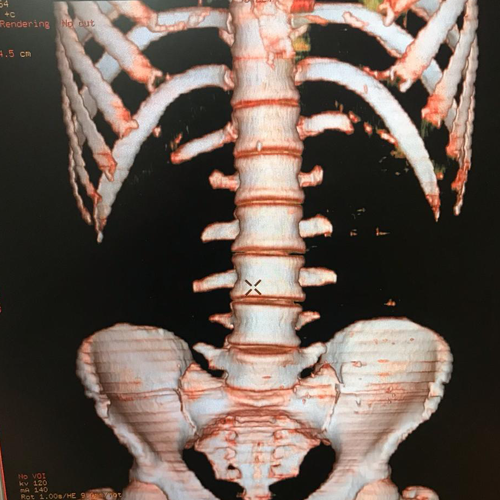

Best Scanning Center In Nakodar